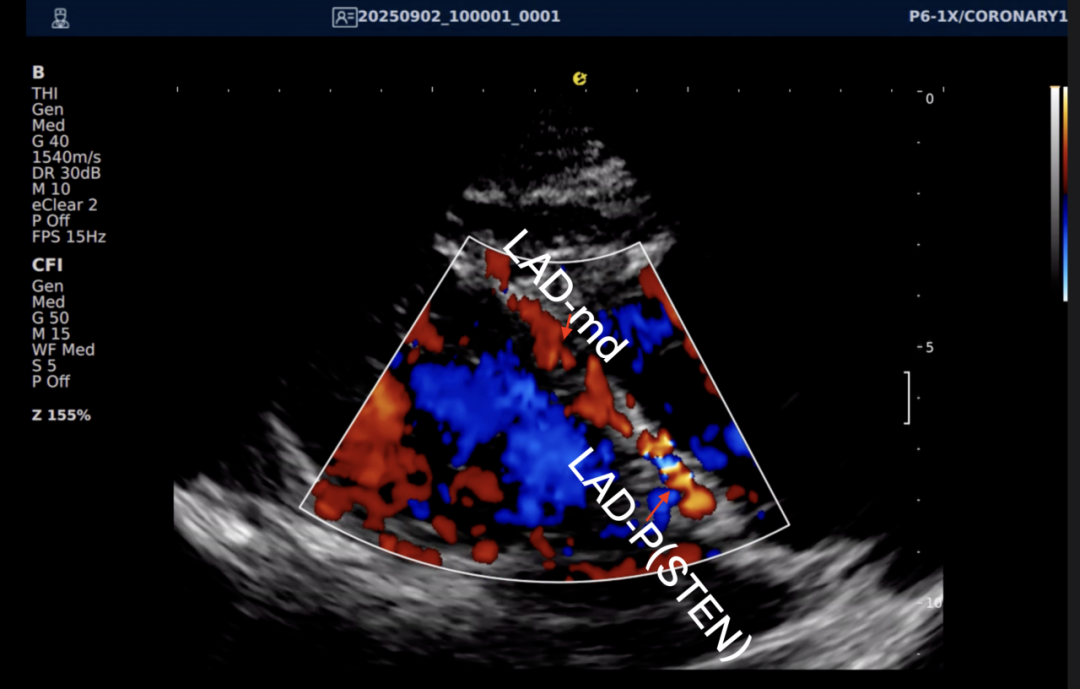

一例胸闷患者,临床采用无创冠脉超声作为初步评估手段,检查中发现:

彩色多普勒:敏感捕捉到局部血流加速现象;频谱多普勒:测得峰值血流速度明显升高,频谱形态异常。

彩色多普勒动态图

彩色多普勒

基于超声提示的异常发现,临床为患者安排了冠脉CTA检查,结果显示前降支近段存在约45%狭窄,与超声提示的血流动力学改变高度一致。

这一病例体现了冠脉超声作为初筛工具的重要价值:它能够无创、实时地评估冠脉血流动力学状态,为后续是否需要进一步影像检查提供重要参考。超声与CTA的协同应用,既能评估结构变化,又能反映功能状态,为临床诊断提供了更全面的信息。